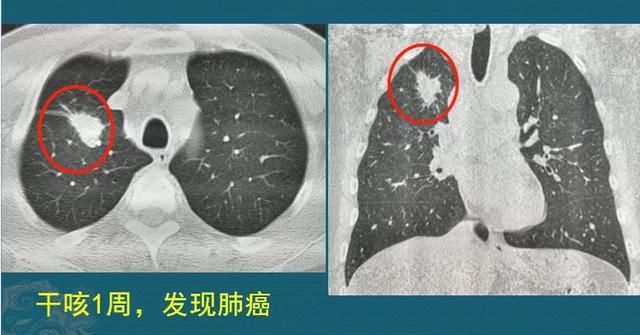

这是一位成年男子,干咳一周发现右侧肺癌,2.2厘米,支气管镜淋投合穿刺以及痰液检查,明确为浸润性肺腺癌,伴有多发转移。

已经无法做根治性手术,选择放弃治疗听天由命,效果 仅仅过了8个月,复查CT显示肿瘤增大到靠近 8厘米,速率 很是快:

现在 病人情形 已经很差,严重消瘦,身体很虚弱,生怕 坚持不了太久了……